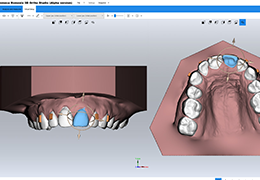

ANYTHINK 经导管主动脉瓣膜置换术分析系统